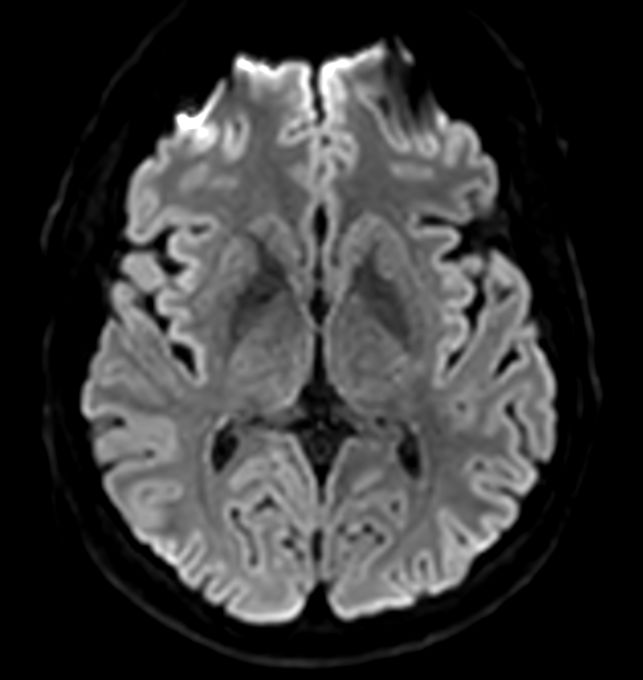

Axial DWI b10.000

-